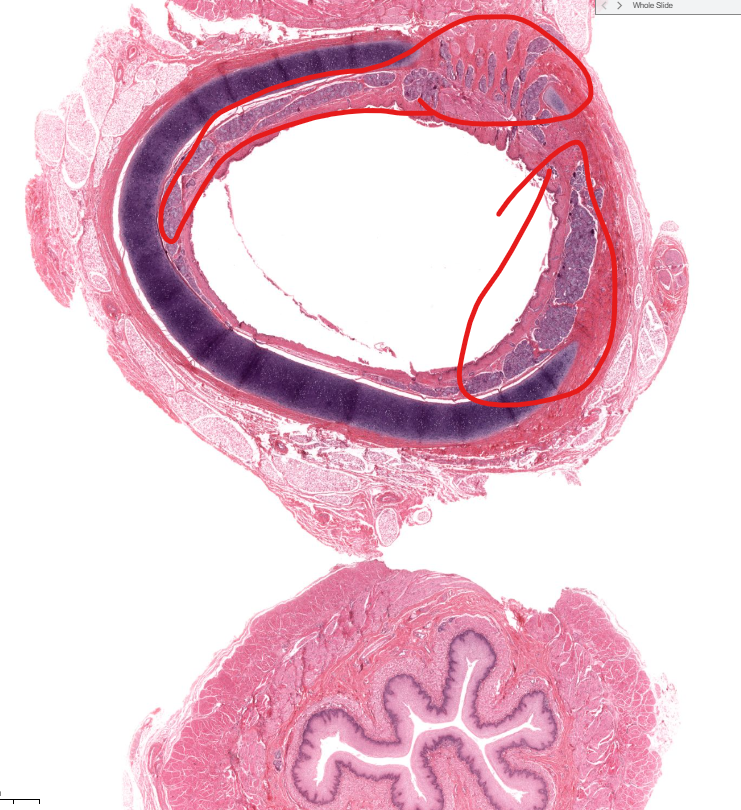

vermiform appendix

notice the absurd amount of lymphocytes

no villi

peyer’s patch

cluster of lymphocytes in the ilium